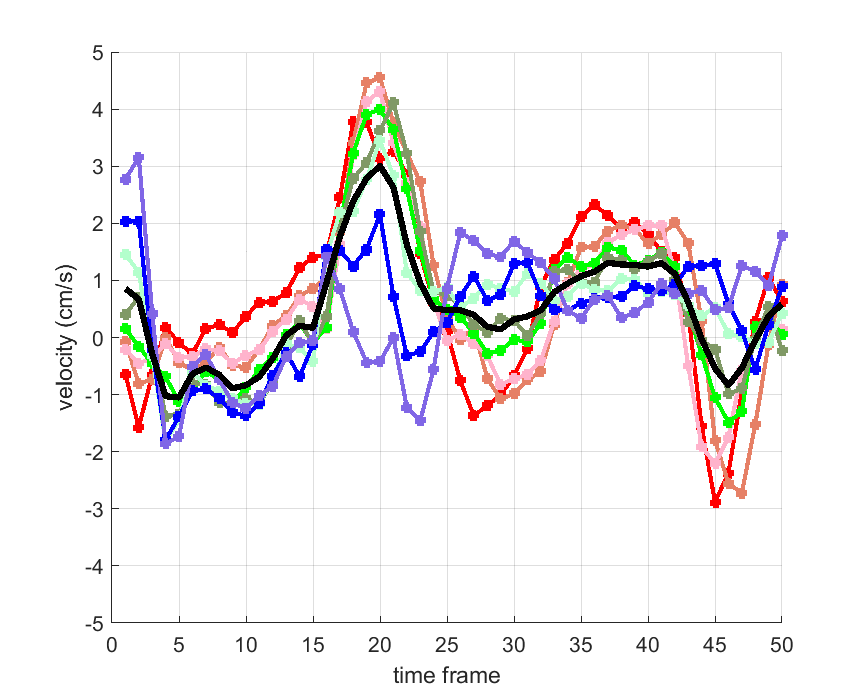

Time courses of the estimated translational component per subject, frame, slice and volume along the 3 velocity directions x, y and z are presented in Fig.6 - Fig.8.